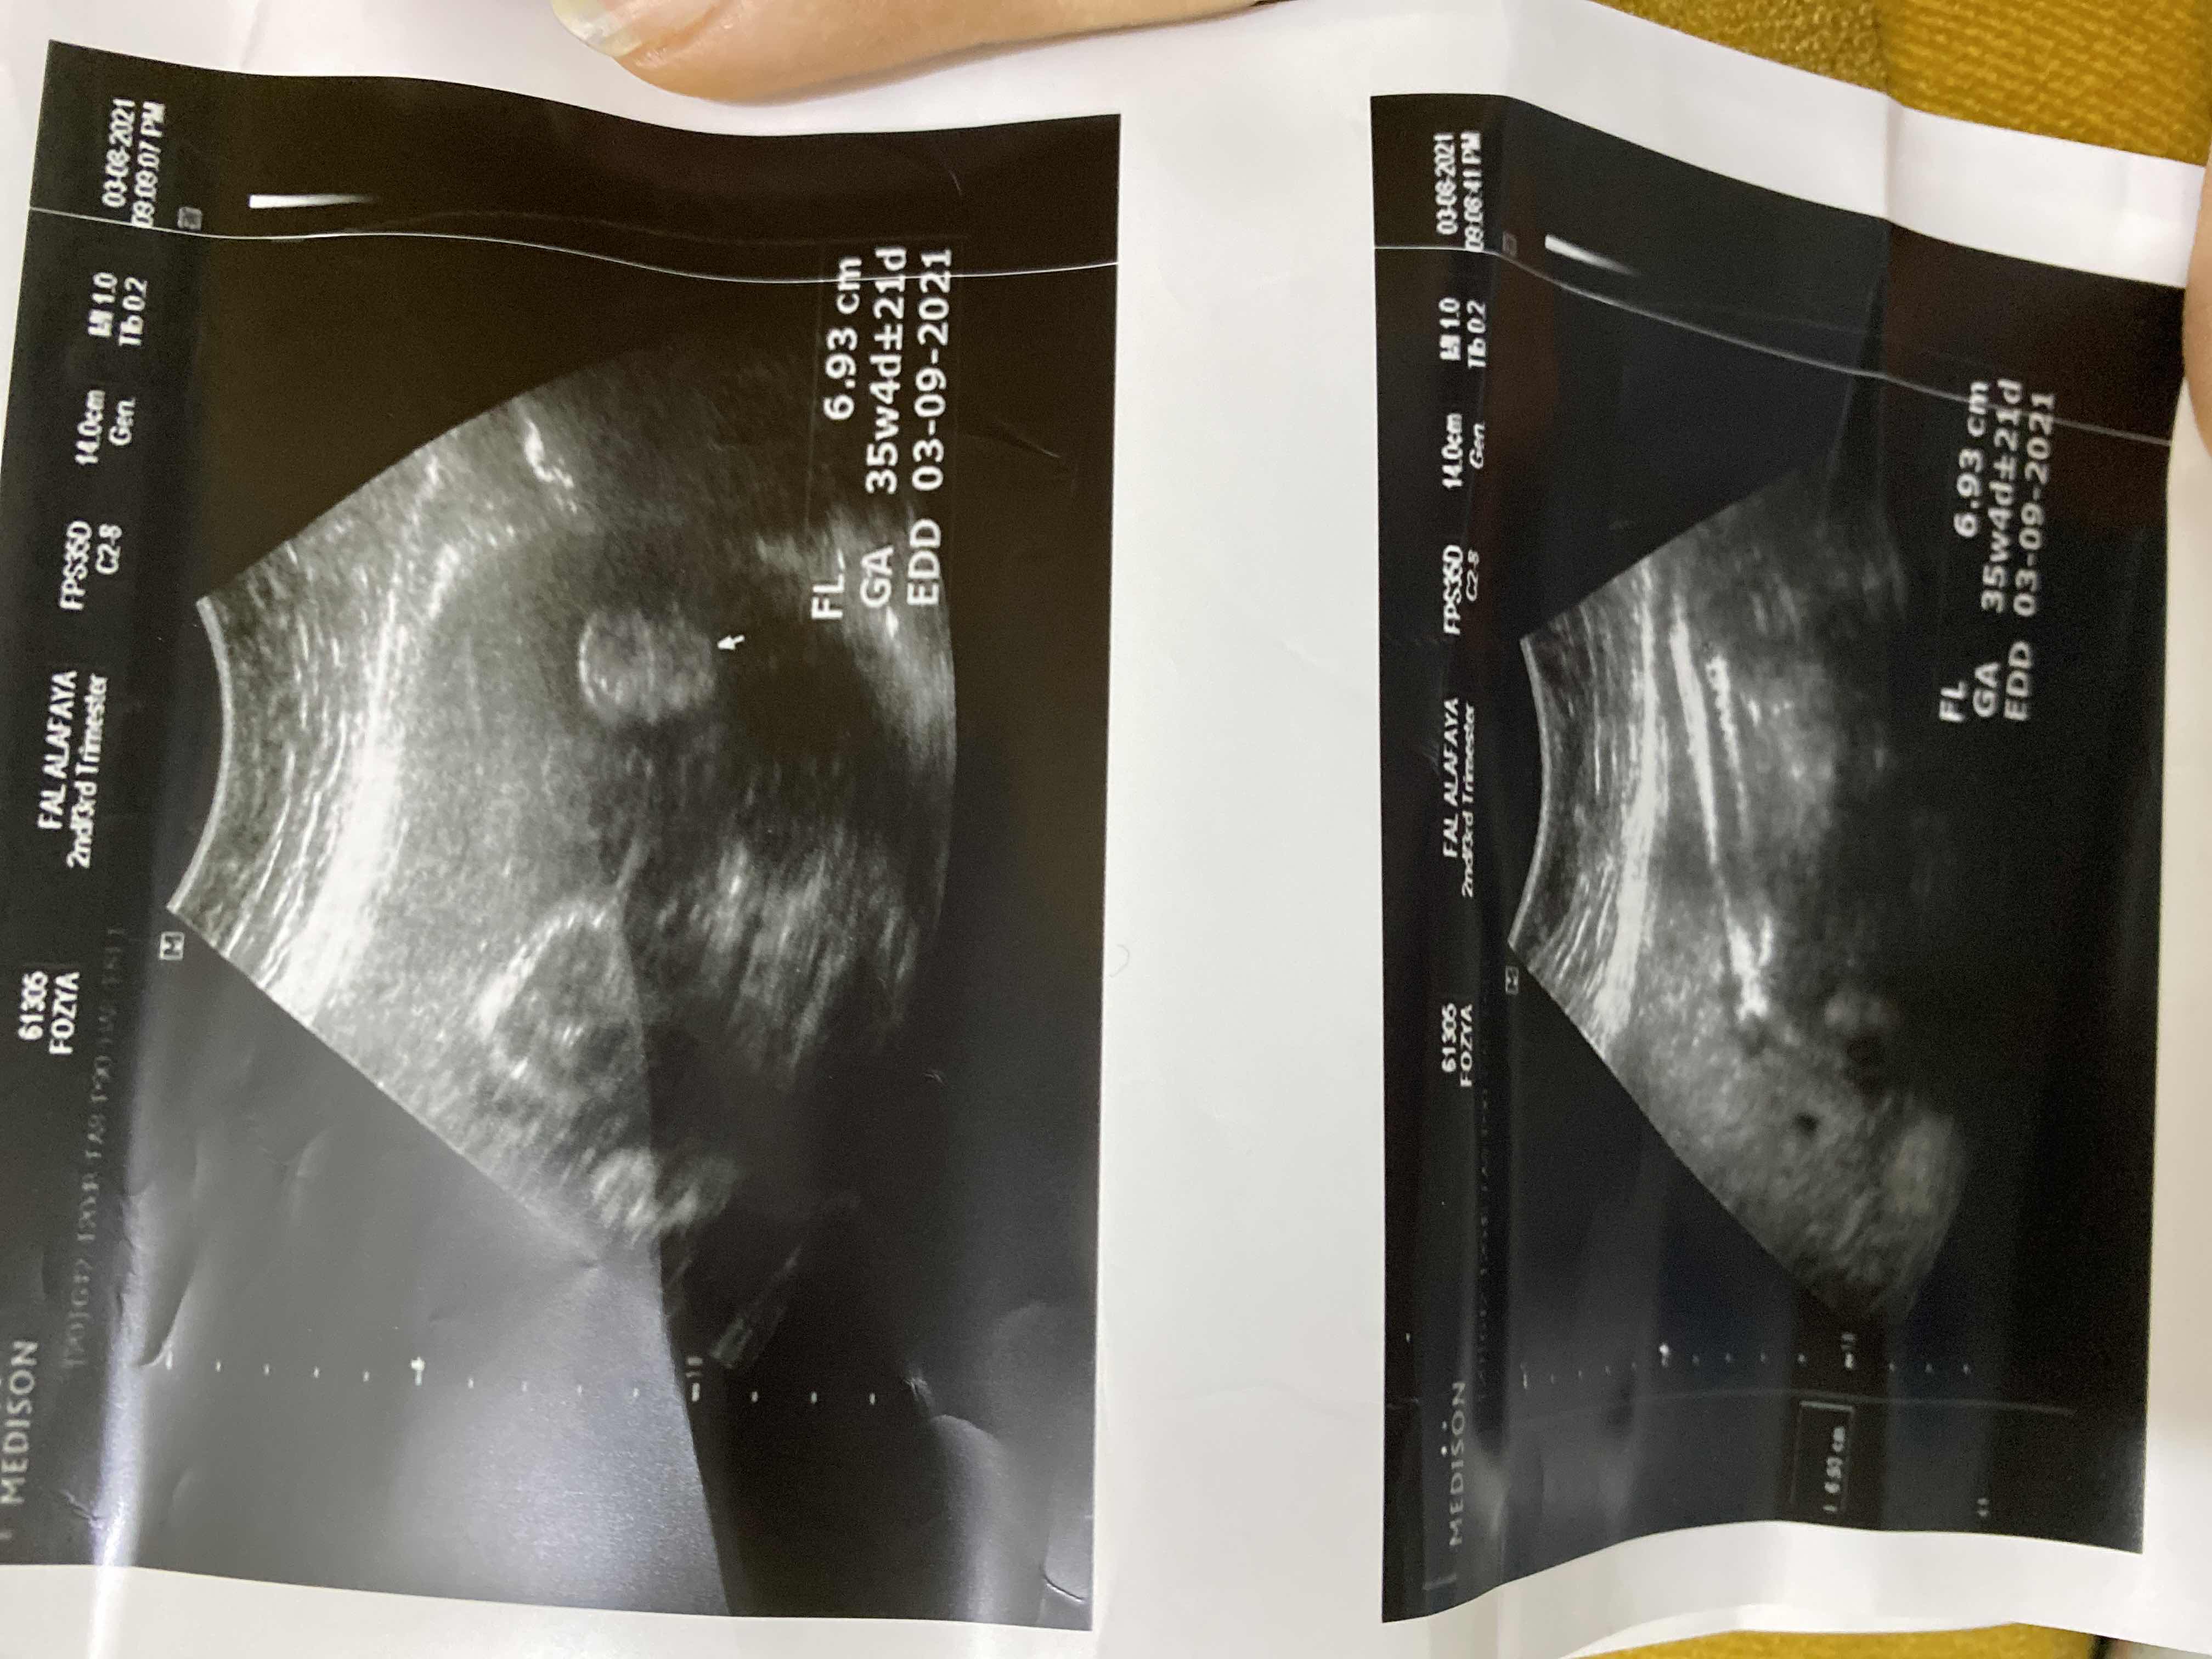

امس سويت سونار وقالت الدكتوره ولد بس مو فاهمه السونار

مو واضح ، اذا اول مره يقولون لك روحي موعد ثاني عشان تتأكدين